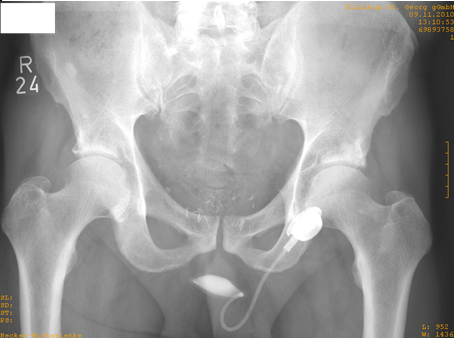

Die Harninkontinenz ist weltweit verbreitet. Der Volksmund spricht auch von „Blasenschwäche“. Es wird definiert als spontanen und unwillkürlichen Verlust von Urin zur ungeeigneten Zeit und Ort. Diese Erkrankung kann beide Geschlechter treffen und hat verschiedene Ursachen, die manchmal alters bedingt, oder infolge iatrogene operative Komplikationen und medikamentöse Einnahme. Bei Versagen der physikalischen und medikamentöse Therapie der männlichen Harninkontinenz wird eine operative plastische Operation bestrebt. Operativ sind verschiedene Operationsmöglichkeiten wie Para-Urethrale Injektionsverfahren, Nicht-Adjustierbare Bänder, adjustierbare Systeme, Artifizieller Sphinkter und Harnableitung möglich. In den letzen Jahren wurde das Sphinkter-System vereinfacht. Das ATOMS-System ist ein perineal implantiertes hydraulisches Sphinkter-Ersatzsystem. Es kommt bei der Aktivierung zur Kompression der bulbomembranösen Harnröhre und die Adjustierung erfolgt über ein Portsystem. Durch 4-Punkt-Fixation wird eine symmetrische Lage um die Urethra geschaffen (siehe Abbildung 10 [Abb. 10]).

Abbildung 10: Lage des ATOMS-Systems

Zwischen März 2010–März 2012 haben wir 21 ATOMS-Implantationen durchgeführt. Das mittlere Patientenalter lag bei 74 Jahre. 17 Patienten zeigten eine signifikante Verbesserung der Inkontinenz und der Lebensqualität (81%). Bei 2 Patienten musste das System wegen einer Infektion explantiert werden. Insgesamt stellt das ATOMS-System eine technische Verbesserung in der Behandlung der männlichen Harninkontinenz dar.